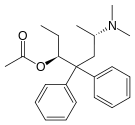

Phenalkoxams

- Dextropropoxyphene (propoxyphene)

- Dimenoxadol

- Dioxaphetyl butyrate

- Levopropoxyphene

- Norpropoxyphene

- Pyrroliphene

Structures

| Phenalkoxams | ||||

|---|---|---|---|---|

Dextropropoxyphene |

|

|

|

|